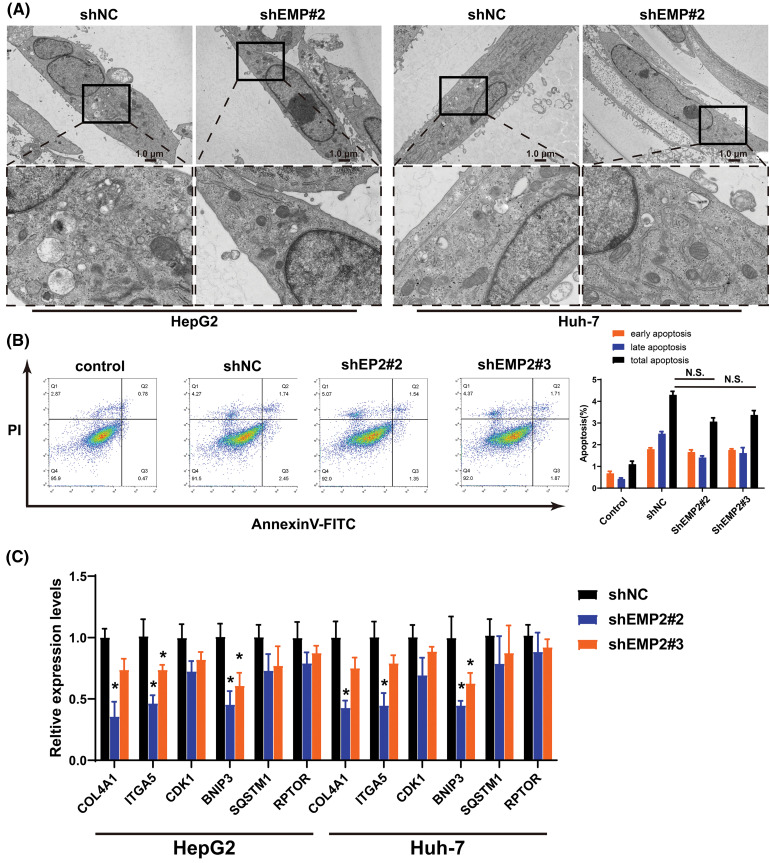

Transient transfection of GFP-LC3 (green fluorescent protein-microtubule associated protein 1 light chain 3) plasmids was performed in HepG2 and Huh-7 HCC cells, and the punctate aggregation of GFP-LC3 fluorescence was observed using confocal microscopy. A significant reduction in the number of GFP-LC3 puncta was observed in the cytoplasm of the shEMP2 group compared to the control group, suggesting that downregulation of EMP2 expression in HepG2 and Huh-7 HCC cells substantially inhibits autophagy (Figs. 5E, 5F). To investigate the cellular ultrastructure, TEM was employed to observe cells in each group. The findings demonstrated that in HepG2 and Huh-7 HCC cells, the number of autophagosomes in the shEMP2#2 group cells was significantly reduced compared to the control group, further corroborating the concept that downregulation of EMP2 expression inhibits autophagy in HCC cells (Fig. 6A). Furthermore, Annexin-V/PI (Propidium Iodide) dual-staining flow cytometry was utilized to assess apoptosis in HepG2 cells following EMP2 silencing. The results demonstrated that cellular apoptosis did not exhibit a significant increase in the EMP2 knockdown group compared to the control group of HepG2 cells (Fig. 6B). These findings suggest that although EMP2 silencing inhibited the proliferative capacity and autophagy in HCC cells, it did not trigger cellular apoptosis.

RT-PCR was employed to detect the mRNA expression changes of collagen 4A1 (COL4A1), integrin α5 (ITGA5), Cyclin-Dependent Kinase-1 (CDK1), and autophagy-related genes, including BCL2/adenovirus E1B interacting protein 3 (BNIP3), sequestosome 1 (SQSTM1 or p62), and regulatory-associated protein of mTOR (RPTOR), which are associated with the extracellular microenvironment. The results demonstrated that in HepG2 cells, downregulation of EMP2 expression led to a significant reduction in both ITGA5 and BNIP3 in the shEMP2 group. COL4A1 was significantly downregulated in shEMP2#2, whereas in the shEMP2#3 group, there was a decreasing trend in COL4A1 expression, albeit not reaching statistical significance. CDK1, SQSTM1, and RPTOR exhibited downregulation in both shEMP2#2 and shEMP2#3 groups; however, no statistically significant differences were observed compared to the control group (Fig. 6C). Western blot was utilized to evaluate the expression of several autophagy-related proteins